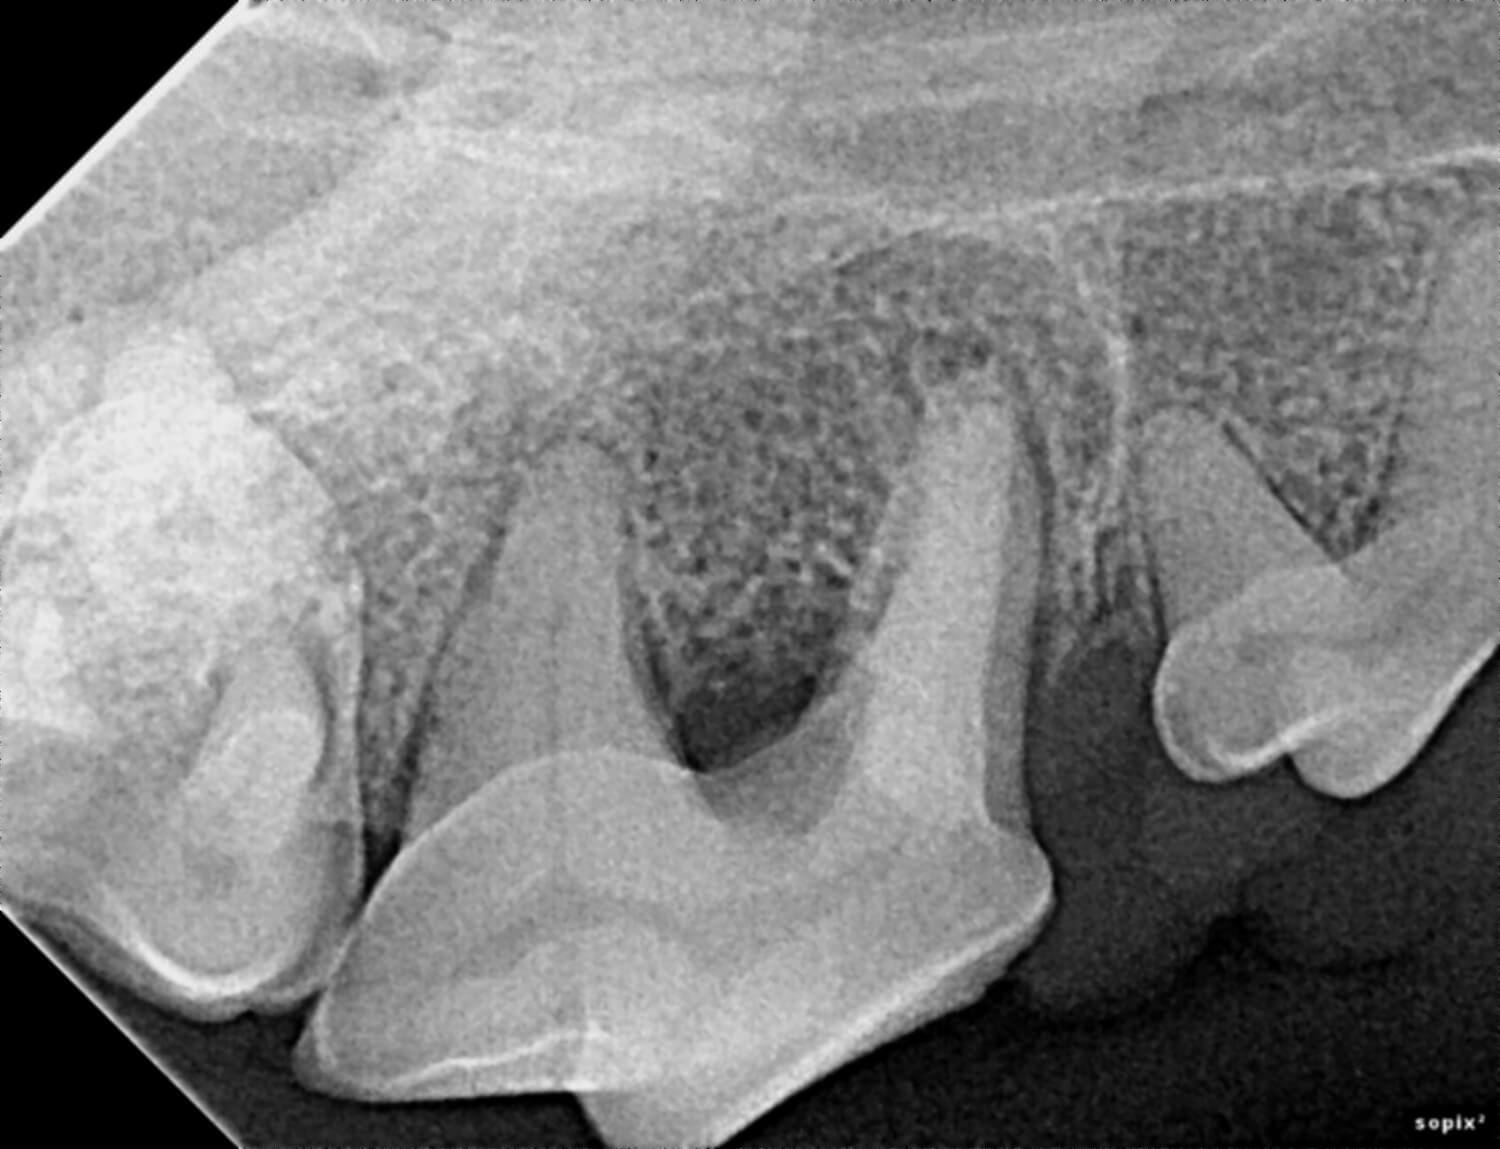

Our veterinarians use digital radiology to detect conditions such as tooth root abscesses, oral tumors, jaw fractures and hidden dental and periodontal issues. Early diagnosis enables timely treatment, reducing pain and preventing advanced dental complications.

Digital radiology plays a vital role in preventive health and advanced diagnosis for pets. Dental and oral conditions are often hidden below the gumline, where physical exams cannot detect them.

This imaging can reveal issues such as periodontal disease, infections, tooth resorption, and bone loss before they cause noticeable pain or lasting damage. Prompt diagnosis allows our team to provide targeted treatments that keep your pet comfortable and healthy.

Digital radiology helps identify dental and oral problems in their earliest stages, often before visible symptoms develop. This means less invasive treatments and better outcomes for your pet.

Digital radiology identifies hidden dental issues such as tooth root abscesses, periodontal disease, jaw fractures, and oral tumors. This allows our veterinarians to diagnose and treat a wide range of oral and dental problems efficiently.